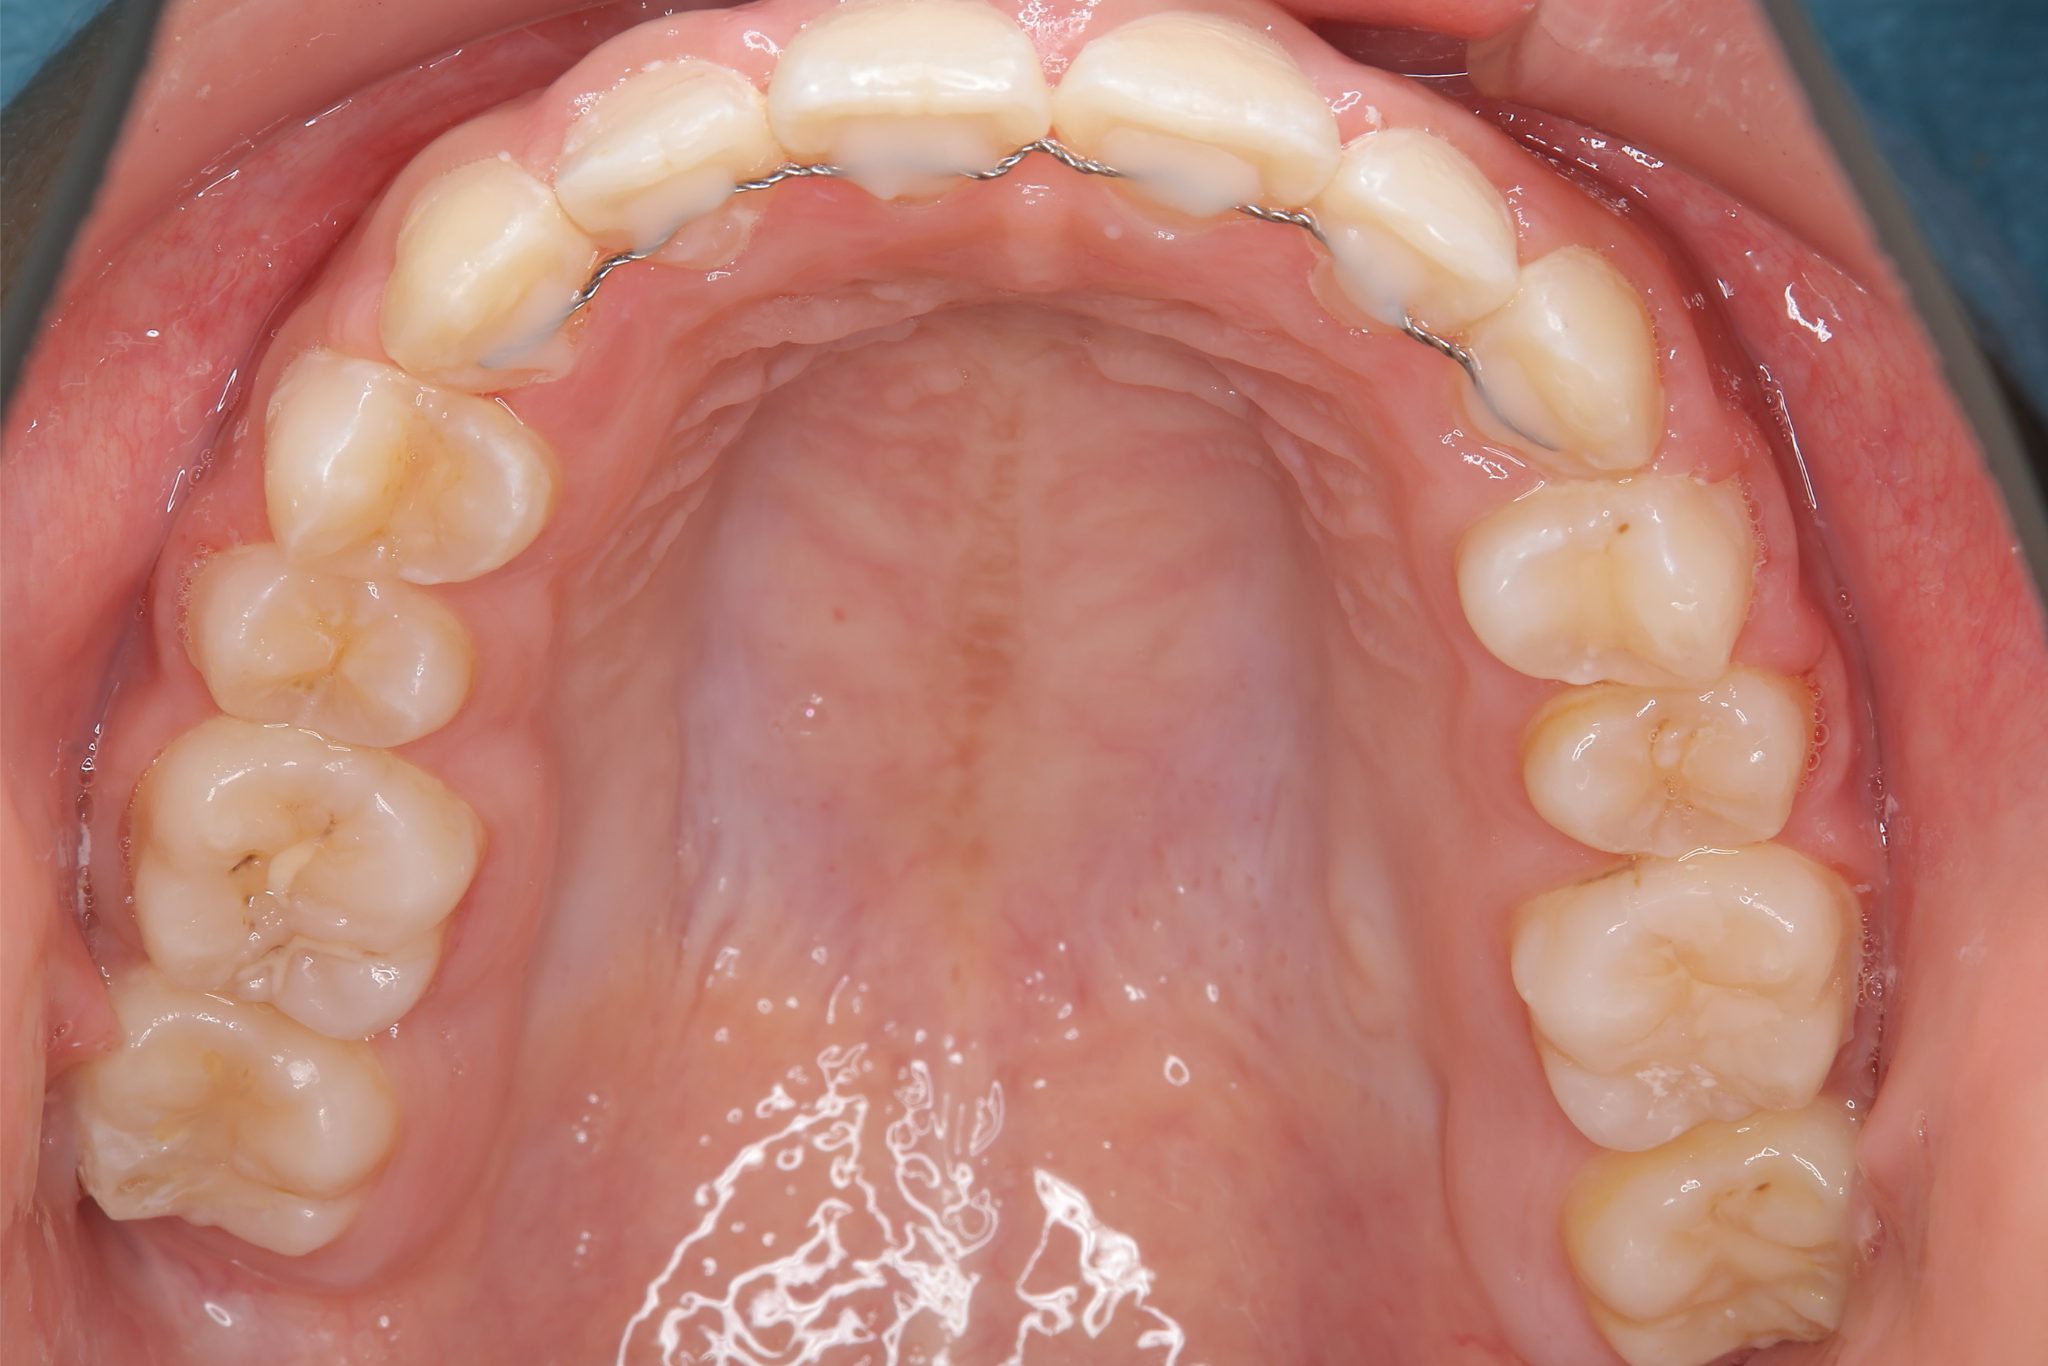

アフター

全顎ワイヤー矯正 症例_474

主訴 歯並びがガタガタで前歯が出ている

施術内容 小児矯正1期治療

治癒期間 1年5か月間

費用 1,020,800円(税込)